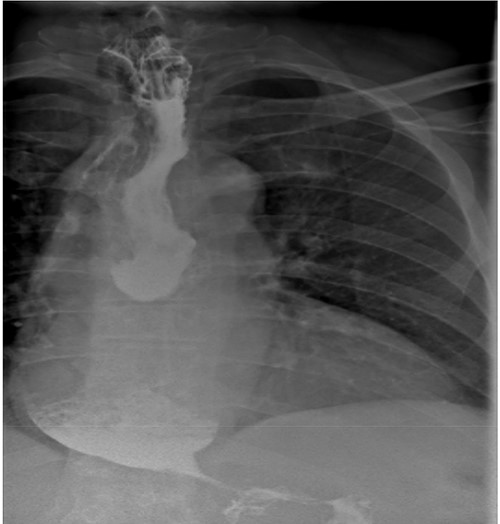

As part of the assessment, computed tomography (CT) coronary angiogram study was performed and it demonstrated a large fluid-filled oesophagus causing partial compression of the left atrium. Barium swallow (Fig. 1A and B), CT chest and abdomen (Fig. 2A and B) and transthoracic echocardiography (TTE) showed a 7.1-cm dilated oesophagus causing left atrial compression and a small hiatal hernia (Fig. 3).

(A) LAGB more inferior and rotated consistent with band slippage; (B) marked distension of the oesophagus and contrast hold up at the level of the slipped band.